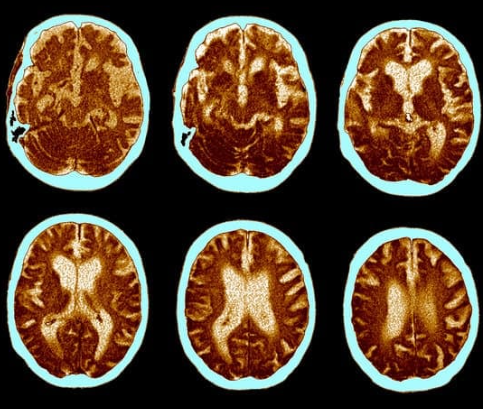

초기 알츠하이머는 신경과 전문의와의 상담을 통해 진단할 수 있으며, 인지 검사와 함께 MRI 또는 CT 스캔을 통해 뇌 구조를 확인하는 과정이 포함됩니다. 이러한 진단 도구들은 뇌의 변화 상태를 파악하는 데 중요한 역할을 하며, 조기 진단이 가능하도록 돕습니다.Q: 알츠하이머 초기 증상과 치매의 차이는 무엇인가요?